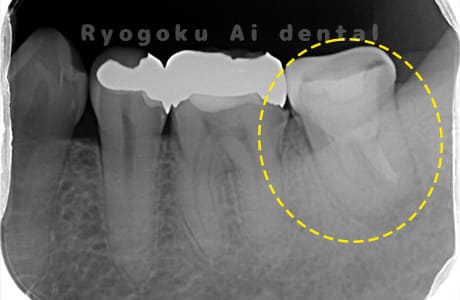

Case02

-

- 原因

- 慢性根尖性歯周炎

- 治療期間

- 1回(消毒・洗浄も含めると3回)

- 治療内容

- 歯根端切除術

- 治療費用

- ¥110,000

他院で抜歯と判断され、インプラント治療を提案された患者様です。被せ物を外さずに、歯の根尖部に外科的にアプローチし、病気の部分を除去しました。

<リスク・副作用>

外科手術のため、術後に出血、痛みや腫れ、違和感を伴います。口腔内の状態によっては適応できないことがあります。歯根端切除で治らなければ抜歯を検討しなくていけない場合もあります。